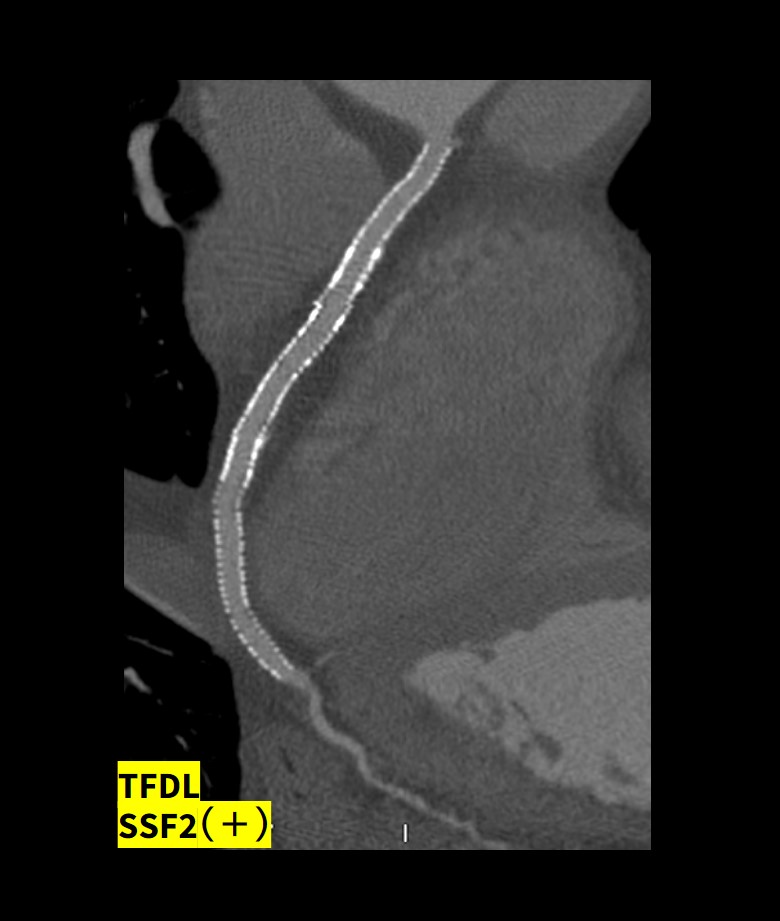

SSF2とTrue Fidelity DLがもたらした圧倒的な画質向上

SSF2の動き補正とともにAscend Eliteに搭載されるDeep learning画像再構成技術(TrueFidelity DL)はステントの内腔評価を格段に向上させている。Fig.7に示す症例は複数のステントがOverlapして留置されているにも関わらず内腔評価は十分に可能であった。

Fig.7 複数ステントが重なる症例におけるステント内腔の描出